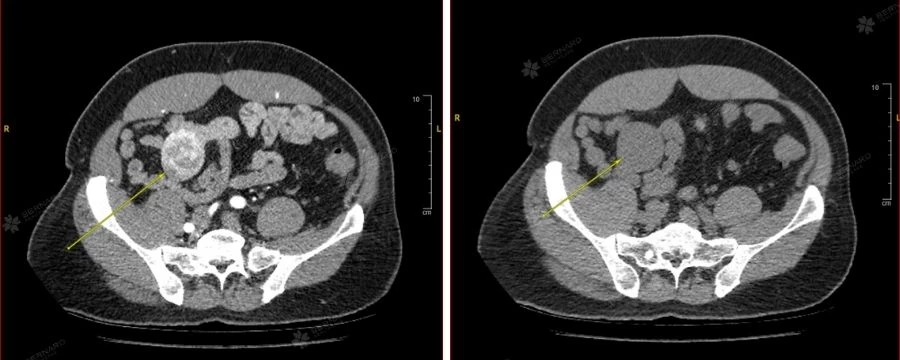

Trong khuôn khổ gói khám sức khỏe tổng quát tại Bernard, anh T. được thực hiện siêu âm bụng nhằm kiểm tra các bệnh lý cơ quan trong ổ bụng. Kết quả ghi nhận một khối giảm âm tại vùng mạc treo ruột dưới rốn, kích thước khoảng 63x35x53mm, bờ đều, giới hạn rõ, không ghi nhận tăng sinh mạch máu. Tổn thương được nghi ngờ là u mạc treo, chưa rõ bản chất, cần theo dõi theo hướng u mô đệm đường tiêu hóa (GIST).

Hình ảnh CT cho thấy tổn thương choán chỗ lớn vùng hố chậu phải, có kích thước 40 x 47 x 65mm (ngang x trước x sau), giới hạn bờ rõ, không xâm lấn xung quanh. Những đặc điểm trên phù hợp với u mạc treo (mesenteric tumors).